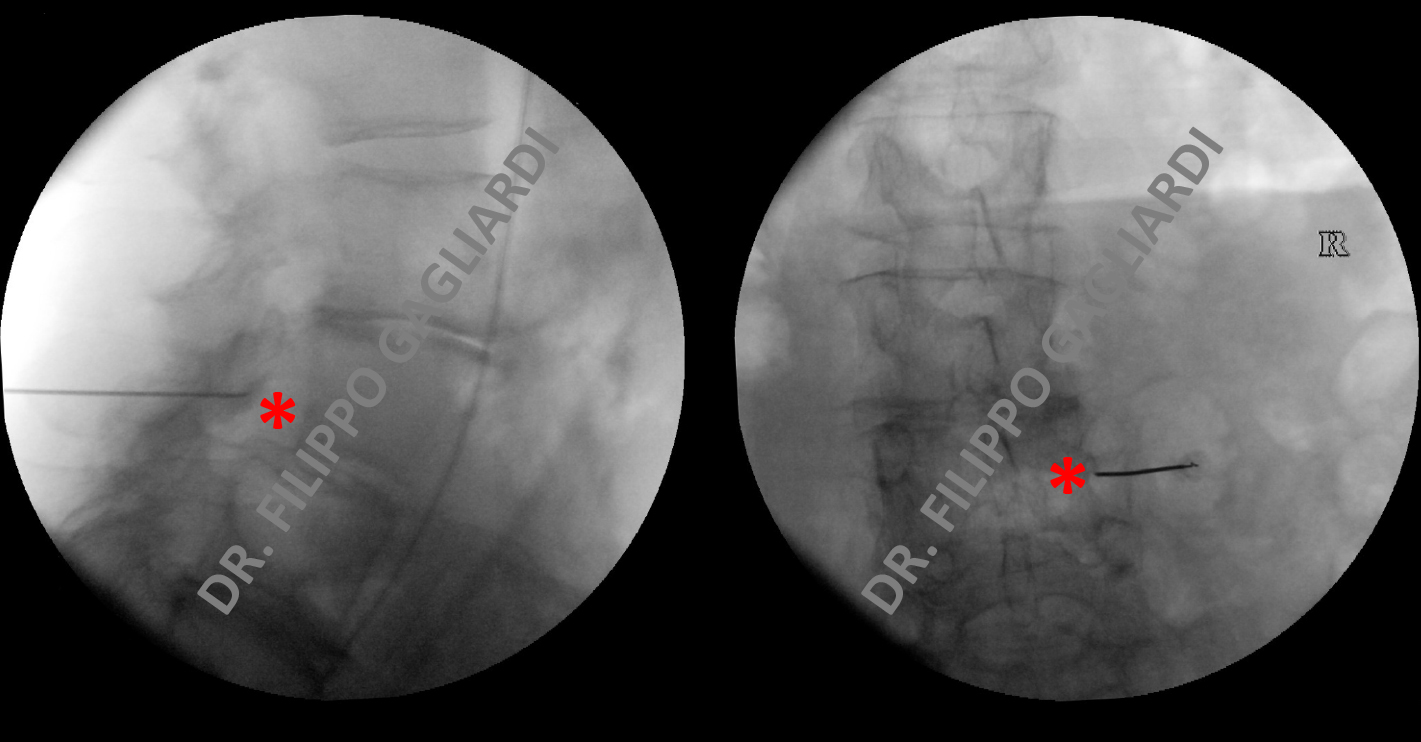

Le infiltrazioni sono delle metodiche che consentono di iniettare quantità definite di farmaci in punti precisi della colonna vertebrale. L'identificazione del punto target o bersaglio avviene attraverso l'ispezione clinica, la visita, l'ecografia o la radiologia (come nel caso qui presentato). Il farmaco può infatti essere alternativamente iniettato:

Nei casi di aderenze attorno alla dura madre (peridurali) in esiti di plurimi interventi alla colonna vertebrale lombare vi sono delle tecniche percutanee mininvasive endoscopiche che consentono di lidere le aderenze (periduroscopia, o epiduroscopia). Il Dr. Gagliardi è specializzato nelle tecniche infiltrative di terapia del dolore, per le quali ha seguito corsi all'estero. Nell'immagine vedete un caso trattato dal Dr. Gagliardi di infiltrazione foraminale di una radice nervosa per trattare in modo conservativo una sciatalgia. Si vede l'ago visualizzato con la radiologia nel punto target (asterisco rosso), ovvero a livello del forame di coniugazione.